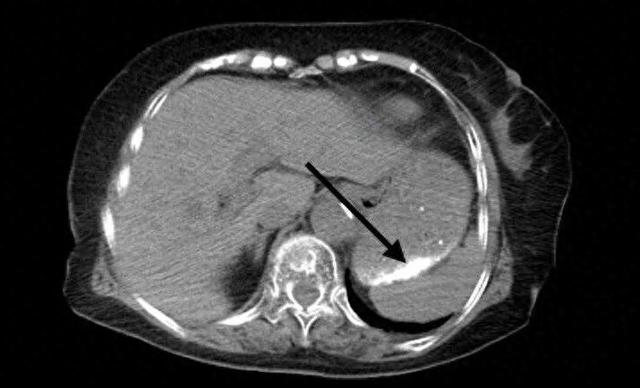

事件概述 - 一名73岁老人误将暖宝宝内黑色粉末当作芝麻糊冲服 随后出现头晕不适被送医[1] - 急诊医生接诊后立即启动应急响应和多学科救治 进行护胃补液等支持治疗并完成腹部CT检查[1] - CT结果显示胃部及部分小肠内有多发致密影 表明粉末已散布于上消化道 存在化学性灼伤 肠穿孔及肠梗阻风险[2][4] - 消化内科医生实施紧急胃镜探查与异物清除术 成功吸除胃内残留粉末[5] - 患者病情得到有效控制 经数日住院观察后已顺利出院[5] 暖宝宝成分与误食风险 - 暖宝宝发热芯材主要由还原铁粉 活性炭 蛭石 氯化钠等物质混合构成[5] - 误食风险主要包括三重:化学性损伤 铁粉在胃酸中氧化放热可能引起黏膜灼伤甚至穿孔[5];物理性风险 粉末可能黏附刺激消化道黏膜 大量积聚可能引发肠梗阻[5];误吸危险 呕吐或吞咽时粉末呛入气管可能导致吸入性肺炎或呼吸道梗阻 对老年人威胁尤甚[5] 误食事件应急处置指引 - 发现误食后应立即送医 并携带误食物品的残余部分和包装 以协助医生判断成分[6] - 切勿盲目催吐 尤其对于腐蚀性物质或意识不清者 以免造成二次损伤或窒息[7] - 应遵从专业处置 医生将根据异物性质与位置决定采取胃镜取出 药物治疗或手术等方案[8] 老年人照护安全建议 - 老年人因认知功能下降易发生误食误服意外[10] - 建议进行“视线管理” 将药品 化学品及小件危险品安全上锁或置于无法触及的高处[11] - 建议简化环境 减少家中容易混淆的杂物[12] - 建议加强看护 确保患者在危险区域活动时处于看护者视线范围内[12] - 建议选择更安全的取暖方式替代 并用简单语言反复提醒危险物品“不能吃”[12]